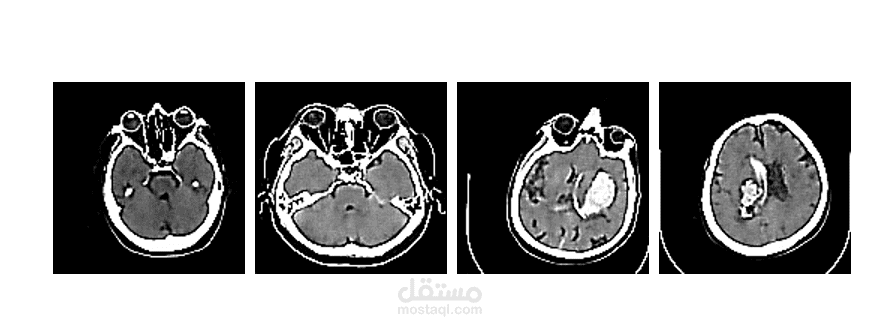

Brain Stroke CT Image Generation: تطوير cVAE لتوليد صور أشعة صناعية لدعم التدريب.

Brain Stroke CT Classification: تصميم CNN (ResNet18) لتصنيف صور الأشعة.